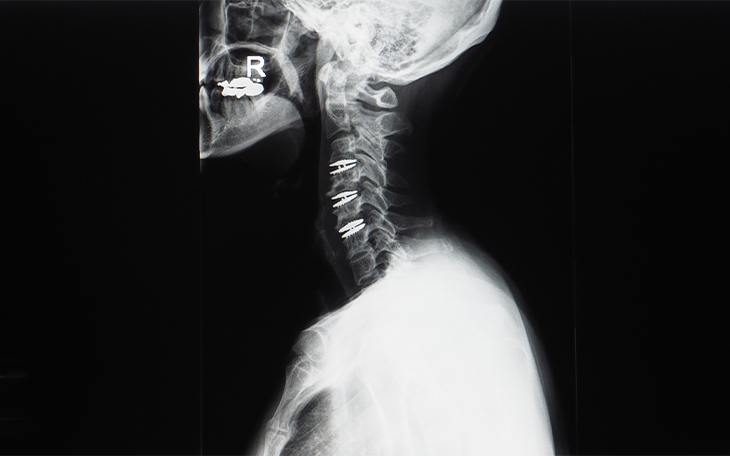

Erkrankungen der Halswirbelsäule

Die Halswirbelsäule (HWS) ist besonders beweglich und zugleich empfindlich gegenüber Fehlbelastungen und Verschleiß. In dieser Kategorie erhalten Sie einen Überblick über häufige Erkrankungen der HWS, deren Ursachen, Symptome und Therapiemöglichkeiten.

Bildquelle: www.docset.de